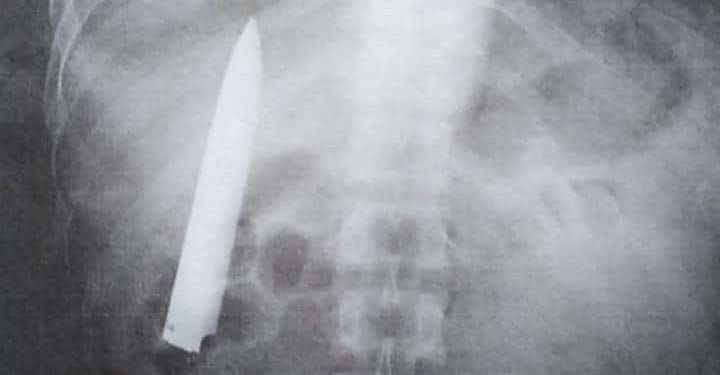

GFC NIEUWSREDACTIE- Een man uit de Filipijnen leefde een jaar lang met een mes in zijn borstkas nadat hij werd neergestoken.

Lad Bible meldt dat de artsen een jaar geleden de wond hadden dicht gehecht zonder het mes te verwijderen, nadat de man het ziekenhuis aandeed voor hulp.

Op 23 maart kwam hij na een medische check-up voor een nieuwe baan tot de ontdekking dat het mes nog steeds in zijn borstkas zat, enkele centimeters verwijderd van zijn longen.

De man eist dat de artsen – die de vergissing hebben gemaakt – alsnog het 11 centimeter lange mes verwijderen. Hij zegt nu pas te weten waarom hij altijd pijn in zijn borst heeft, voornamelijk op koude dagen.

Foto: Viral Press